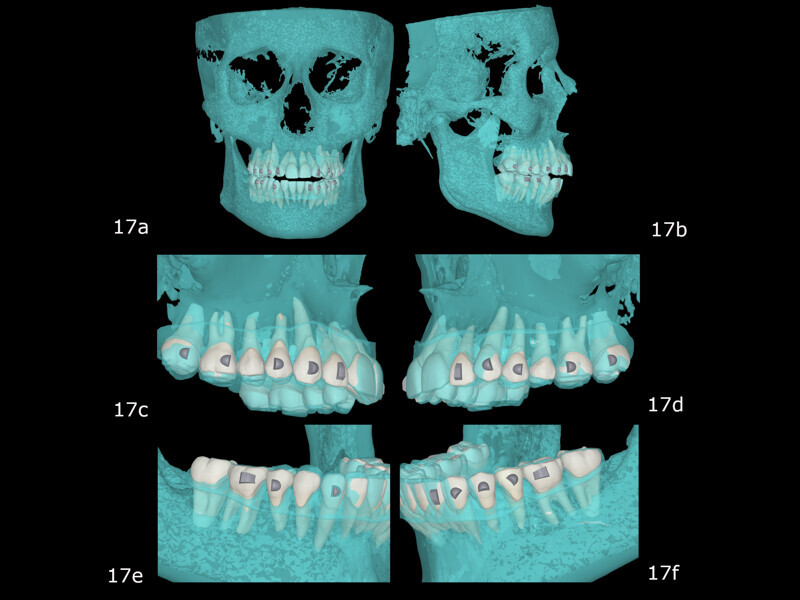

Treatment with the FAS Aligner System, as shown in the FAS OcclusalDesign tool (Fig. 16), was used, aiming at decreasing the vertical dimension through intrusion of the maxillary molars, correcting the arch form, centring the mandibular midline and levelling the maxillary and mandibular occlusal planes. The Bolton discrepancy would be resolved with inferior interproximal reduction. The planned movement was compatible with periodontal health, being within the biological limits of the patient’s alveolar bone (Fig. 17).

Initial treatment in 29 stages was planned, by which point the final occlusal results would have been obtained. We began with the placement of attachments and micro-screws in the maxillary arch for posterior intrusion (Fig. 18). After seven months of treatment and in the 20th stage, we introduced the FAS STOP and GO concept and took new records to prepare for the second phase of aligner treatment (Fig. 19). Thanks to STOP and GO, it is possible to achieve better tracking so that aligners fit properly and shorter treatment times using fewer aligners. This is the advantage of planning in different stages. It helps us achieve all our treatment goals on a consistent basis, and treatment efficiency is much higher.

The second phase of treatment began with the placement of new attachments (Figs. 20–22) and consisted of 12 stages, during which we continued to intrude the maxillary molars, centre the mandibular midline and level the occlusal planes. This phase lasted for four months. The total treatment involved 32 stages over 11 months, and all the treatment goals were achieved (Figs. 23–25).